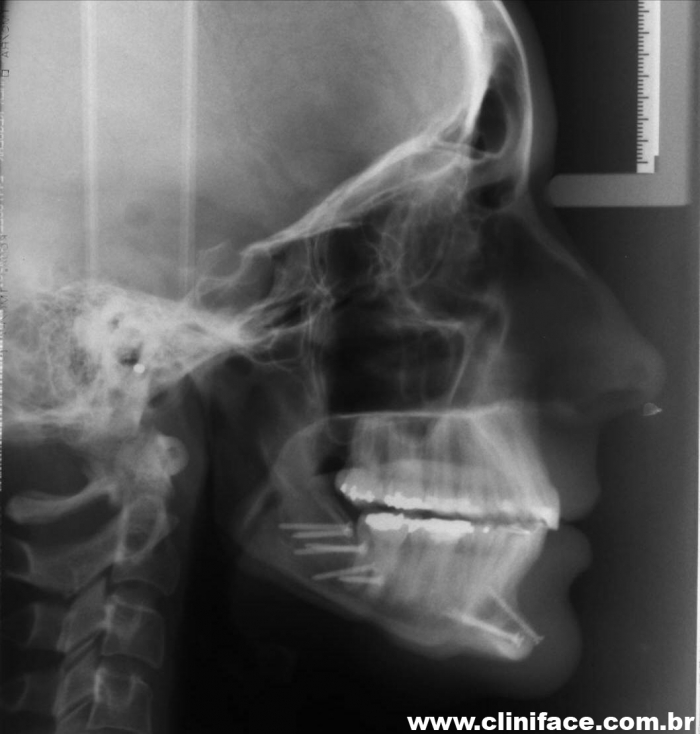

Teleradiografia inicial